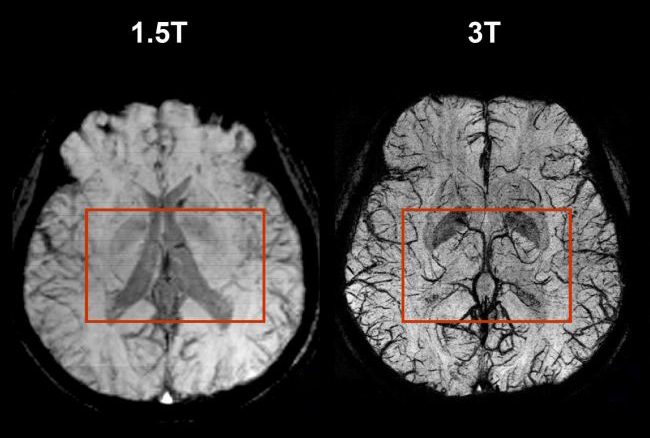

ในการตรวจด้วยเทคนิคเครื่องสร้างภาพด้วยสนามแม่เหล็กไฟฟ้า Magnetic Resonance Imaging (MRI) เราปฏิเสธไม่ได้เลยว่าคุณภาพของภาพ MRI ขึ้นอยู่กับความแรงของสัญญาณและสนามแม่เหล็กเป็นปัจจัยหลักในการให้ความละเอียดและชัดเจนของภาพ ยกตัวอย่างเช่น เดิมเครื่อง MRI 0.5 Tesla ย่อมมีความแตกต่างในการให้รายละเอียดของภาพและความเร็วในการตรวจต่างจากเครื่อง 1.5 Tesla ที่ดีกว่า ซึ่งปัจจุบันด้วยเทคโนโลยีความแตกต่างนั้นก็เป็นเฉกเช่นเดียวกันกับเครื่อง 3 Tesla ที่ให้ความแรงสนามแม่เหล็กเป็นสองเท่า เมื่อเทียบกับเครื่อง 1.5 Tesla ผลที่ตามมาย่อมให้สัญญาณภาพที่มากขึ้น ความเร็วในการตรวจที่เร็วขึ้น เนื่องจากการมีความแรงของสัญญาณเป็นสองเท่า ทำให้ MRI 3 Tesla ให้ภาพที่ชัดเจนและคมชัดมาก นอกจากนี้สามารถทำให้ใช้เวลาตรวจเร็วขึ้น ลดเวลาในการสแกนโดยรวม โดยทั้งสองเป็นสิ่งที่มีค่าอย่างยิ่งสำหรับผู้ป่วยในแง่ของการวินิจฉัยและความสะดวกสบาย

1. การตรวจทางด้านระบบประสาทสมอง (Neuro) Brain & Vascular ชึ่งจะให้รายละเอียดสัญญาณภาพที่ชัดเจนเป็นอย่างมาก ความเปรียบต่างของเนื้อเยื่อสมอง รายละเอียดของเส้นประสาท รวมไปถึงการเก็บสัญญาณภาพของหลอดเลือดภายในสมองที่ไหลเวียนอยู่ ก็สามารถทำได้ดีกว่าเครื่อง 1.5 Tesla ดังนี้

- ให้ความละเอียดของภาพได้ดีกว่า ทำให้เพิ่มความไว (Sensitivity) และความแม่นยำ (Accuracy) ในการวินิจฉัยโรค เช่น โรคสมองขาดเลือด (Stroke) หรือโรคเอ็มเอส (Multiple sclerosis)

- ในการตรวจเส้นเลือด สามารถสร้างภาพหลอดเลือดละเอียดกว่า ทั้งในกรณีก่อนและหลังการฉีดสารทึบรังสี โดยใช้เวลาตรวจที่เร็วกว่าอีกด้วย